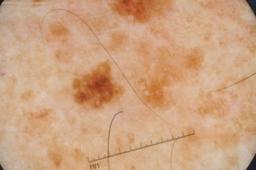

Evaluation set from the ML challenge: SIIM-ISIC Melanoma Classification.